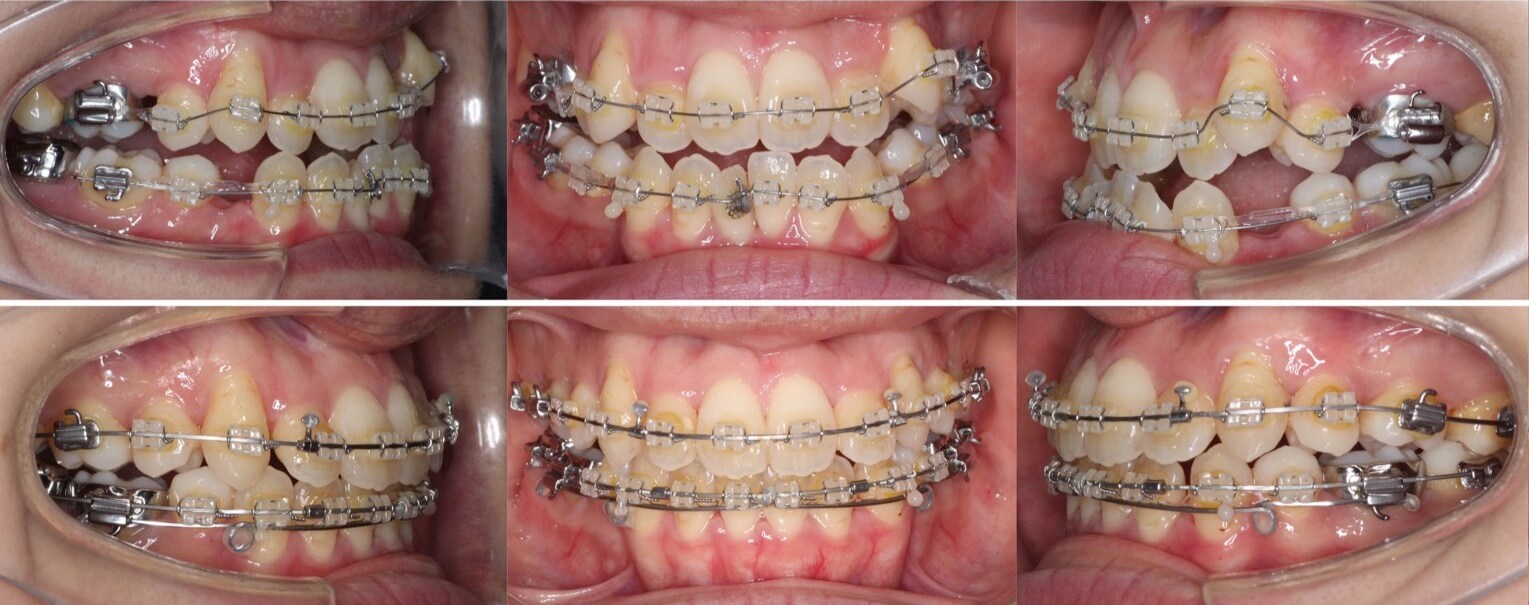

20代女性・唇側矯正装置・上下抜歯

八重歯があり上の歯並びに強いがたつきがある受け口ケースです。反対咬合で小臼歯を抜歯する際は上は5番を抜歯することが多いです。これは、上の前歯を後ろに引きすぎないようにするためです。下の歯並びには前歯の後方移動を効率化するために、2本ワイヤーを使用しています。

<症例概要> 難易度 ★★★★☆

主訴:受け口・前歯のガタガタ

年齢・性別:大学生女性

住まい:千葉県八千代市

症状:反対咬合・重度叢生

治療方針:上下小臼歯抜歯・上顎歯列拡大・空隙閉鎖

治療装置:唇側矯正装置

固定装置:上リンガルアーチ・III級顎間ゴム

抜歯:上第二小臼歯・下第一小臼歯(計4本)

治療期間:2年3か月

リテーナー:上下フィックスタイプ+プレートタイプ

治療費用:990,000(税込)

代表的副作用:痛み・治療後の後戻り・歯根吸収・歯髄壊死・歯肉退縮